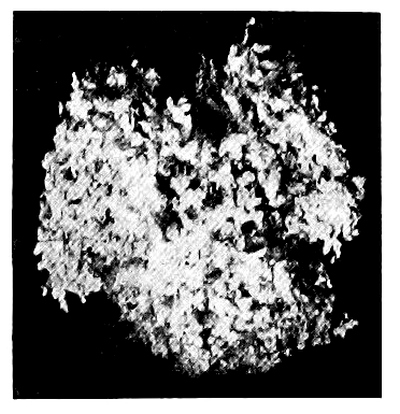

10. Photo-micrograph of Red Blood Corpuscles from Domestic Fowl 99

11. Photo-micrograph of Blood Corpuscles of Fish 99

12. Photo-micrograph of Blood Corpuscles from a Dried Stain of the Blood of a Cod-fish 100

13. Photo-micrograph of a Frog‘s Blood showing oval nucleated Red Corpuscles 101

14. Photo-micrograph of Crystals of Hæmin 102